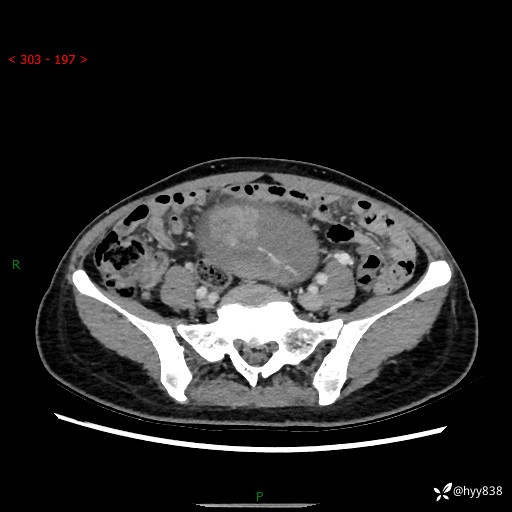

【患者信息】:女,50岁

【主诉】:外院超声发现腹盆肿块,为进一步诊治来我院,门诊已“盆腔肿块”收入院。

腹盆CT平扫+增强

【临床诊断】:盆腔肿瘤